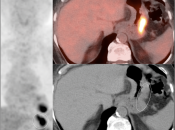

• The utility of PET/CT lies in its assessment of regional nodes and distant metastatic disease.

• Distant Disease: Most commonly to the liver, peritoneum, lung and bone.

• Obviously, signs of associated metastatic disease on the scan give the radiologist much greater confidence in reporting a suspected primary gastric lesion.